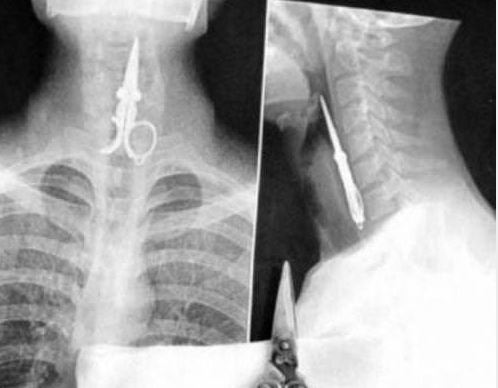

Doktorların görüp yok artık bu nasıl mümkün olur dedikleri röntgen filmleri..

Doktorluğun zor bir meslek olduğu malum. Üstelik bu mesleğin icra ederken bazı zamanlar öyle vakalar ortaya çıkmış ki, doktorlar bile anlamlandırmakta zorluk çekmişler.